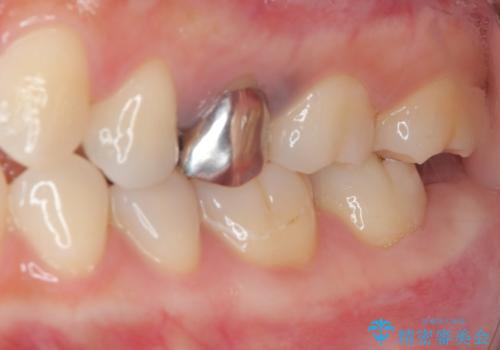

- 笑った時に目立つ銀歯を治したいとのことで来院された患者様です。検査の結果、オールセラミッククラウンによる補綴治療を行っていくことにしました。

拡大鏡視野下で銀歯を外し、オールセラミッククラウンに適した形に整えました。

歯と歯茎の間に圧排糸と言われる糸を入れてシリコーン印象材にて型どりをしました。